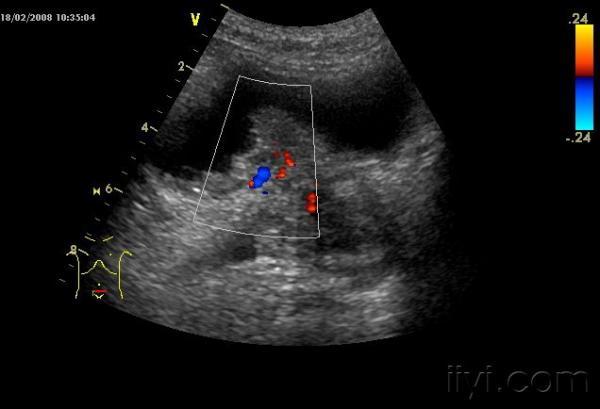

另一处

肿瘤内血供